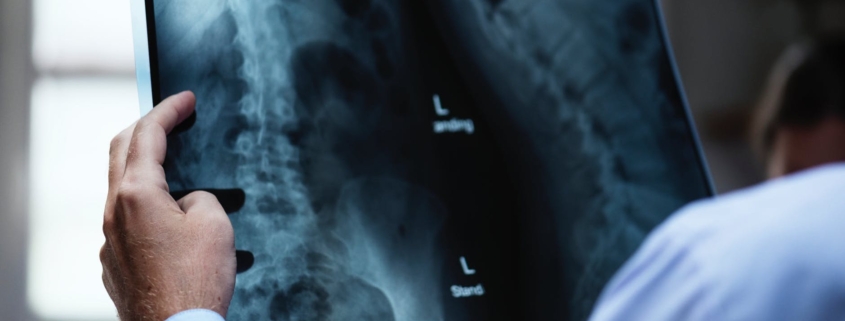

According to a recently released summary of the research, there is a 66% chance that WITHOUT SURGERY your disc herniation will resolve.

Researchers looked at all the studies on this between 1990-2015. Different studies reported differing levels of resolution, with one saying up to 82% of people in their group got better with treatment and exercise and rest; no need for surgery!

We’ve certainly seen surgeons attitudes towards alternatives like seeing another health practitioner, doing back exercises, and keeping active, change over the last few years. It used to be a given that if you had a scan of your back and it showed a disc herniation, that you would have surgery recommended for you. Increasingly we have patients come in telling me that their surgeon saw a disc herniation on their scan and told them NOT to have surgery but instead to come and get treatment.

So bear this in mind if you or someone you know has a disc herniation. There are many factors to be considered but it’s good to know that without surgery, across 25 years of research, it has been found that two out of every three people get better without the need for surgery. If you have any questions feel free to email us harleyplacehealth@gmail.com